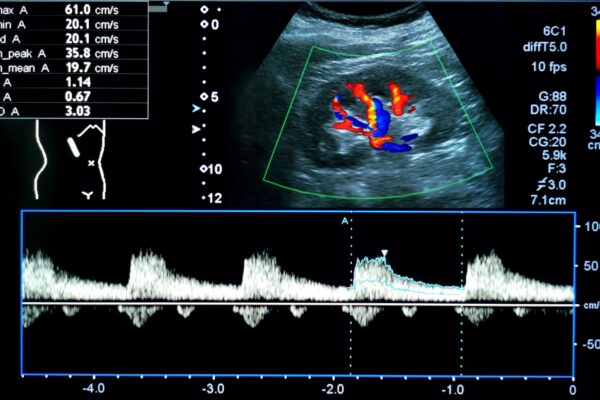

Duplex- und Dopplersonographie

Duplex- und Dopplersonographien sind spezielle Ultraschalluntersuchungen, mit denen Arterien und Venen, also Blutgefässe, beurteilt werden können. Der Schallkopf sendet Wellen in einer bestimmten Frequenz aus, die Wellen werden von den Blutkörperchen und den Gefässwänden in einer veränderten Frequenz reflektiert. Diese Veränderungen der Frequenzen hängen u.a. von der Bewegung der Blutkörperchen ab. Dadurch kann die Richtung des Blutflusses und die Fliessgeschwindigkeit des Blutes bestimmt werden. Dem Arzt ist es dadurch möglich, Einengungen (Stenosen) oder Verschlüsse von Blutgefässen zu erkennen. Die Methode ist völlig risikofrei und eignet sich zur Untersuchung sämtlicher Blutgefässe am Hals, an den Extremitäten (Arme und Beine) sowie im Bauchraum.

Anwendungsbeispiele

- Venenthrombosen an den Beinen (Venenverstopfung durch Blutgerinnsel)

- Arteriosklerose (Gefässverkalkungen durch Ablagerungen von Kalk und Fetten in den Arterien) zB bei den Halsgefässen zur Vorbeugung eines Hirninfarktes